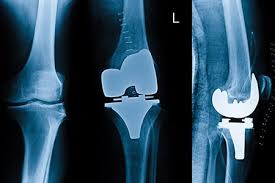

Introduction: Why Knee Replacement Surgery in Korea Is Globally Trusted To begin with, knee replacement surgery in Korea has become one of the most advanced orthopedic solutions for patients...

Introduction Knee pain is one of the most common complaints among adults, especially those with arthritis, injuries, or age-related degeneration. Chronic pain, stiffness, and limited mobility can significantly affect...